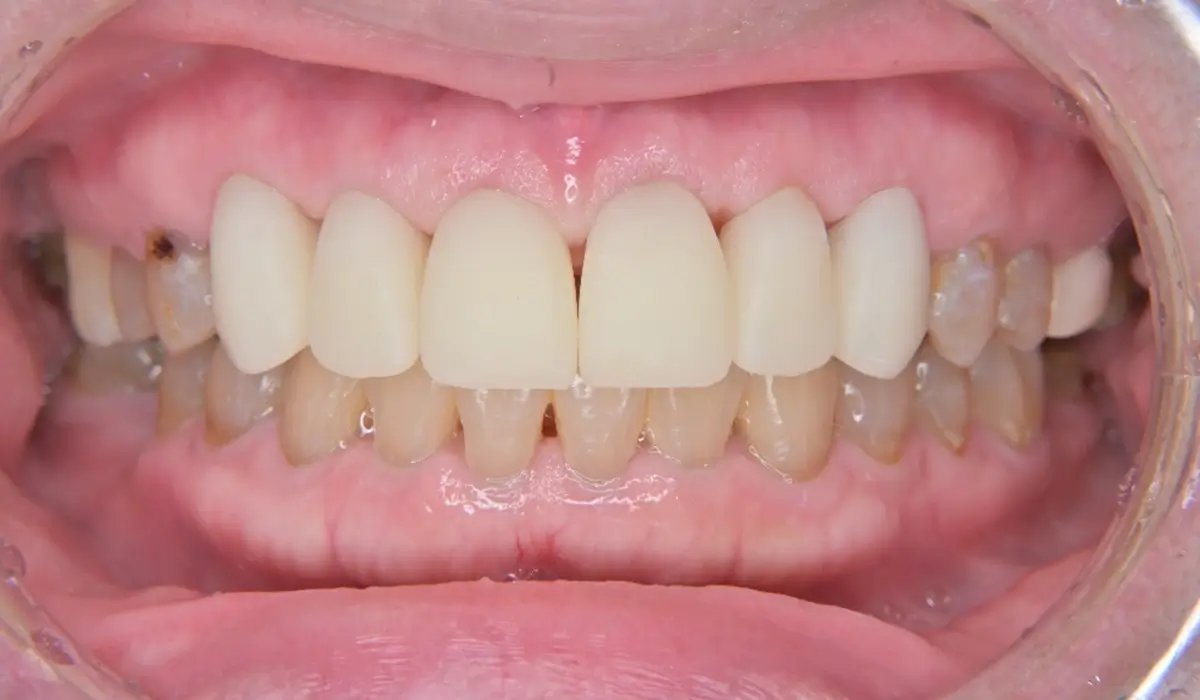

セカンドプロビジョナルレストレーションではより最終形態に近づけた歯冠形態となっています。最終補綴物の形態を術者・技工士・患者様ともにイメージを共有して形態を決定していきました。

セカンドプロビジョナルレストレーションから最終補綴物へ移行するにあたりブラックトライアングルの修正が課題として挙げられます。

ブラックトライアングルとは歯と歯の間の歯肉(歯間乳頭)が下がってしまうことで黒い三角形のすき間が見えてしまうことを指します。ブラックトライアングルの原因としては歯周病や矯正治療、加齢的な変化、不適切なブラッシングによる影響が挙げられます。

本症例では歯周治療の歯肉変化とプロビジョナルレストレーションによる影響で生じたと考えられます。しかし、適切な診査・診断と最終補綴物の設計によりブラックトライアングルを治療することが可能です。